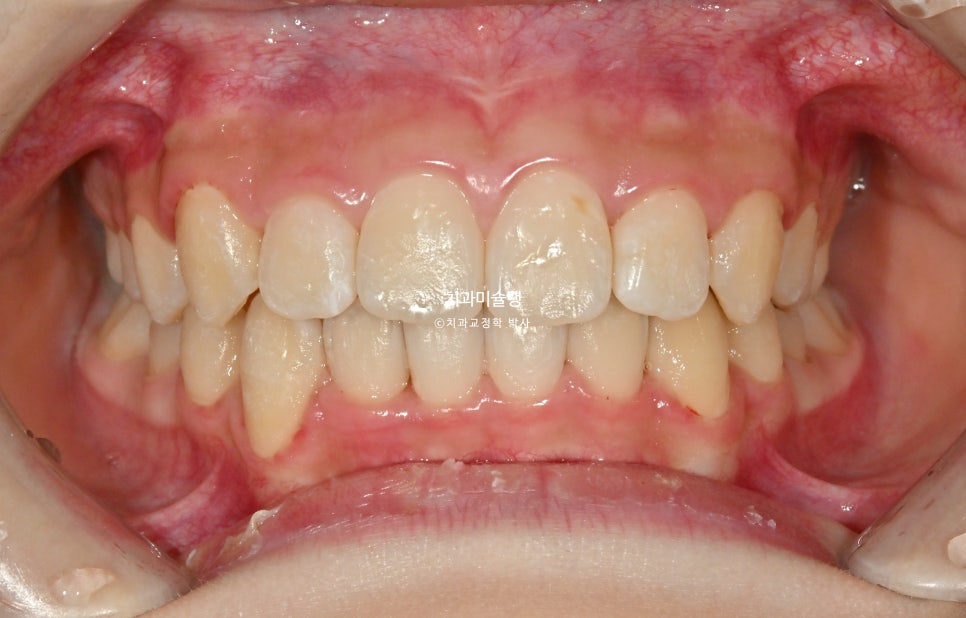

이제 전후비교 보겠습니다.

2023.07-2025.12

고무줄을 잘 껴준 덕에 중심선은 정확히 맞아졌으며 깊게물리던 과개교합도 완전히 개선되었습니다.

어금니 교합관계는 양쪽다 1급을 달성.

결과가 성인교정 결과에 준한만큼, 유지장치도 고정식 철사 유지장치과 가철식 유지장치 두가지 다 성인과 동일하게 들어갑니다.

총 기간은 2년 5개월, 재제작은 1회 했습니다.

재제작을 위한 내원 이외에 따로 중간체크는 없었으며 내원간격은 1년-1년반 이었습니다.

치료 결과

과개교합, 중심선의 개선.

앞니 돌출의 개선

2급 교합관계가 1급 교합관계로 개선되었습니다.